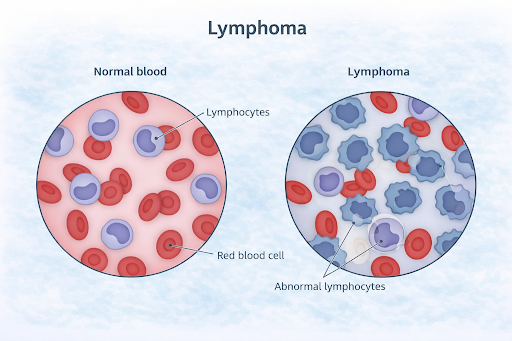

What are Blood Cancers and Lymphomas?

Blood cancers are a group of cancers that affect the blood, bone marrow, or lymphatic system. Lymphomas are a type of blood cancer that primarily involves the lymphatic system, which plays an important role in immunity. These cancers occur when certain blood-forming or immune cells begin to grow and behave abnormally.

Blood cancers are a group of cancers that affect the blood, bone marrow, or lymphatic system. Lymphomas are a type of blood cancer that primarily involves the lymphatic system, which plays an important role in immunity. These cancers occur when certain blood-forming or immune cells begin to grow and behave abnormally.

Where It Begins

Blood cancers and lymphomas may begin in:

Because these systems are interconnected, abnormal cells may circulate or appear in multiple areas.

- Bone marrow, where blood cells are produced

- Bloodstream, which carries cells throughout the body

- Lymphatic system, including lymph nodes, spleen, thymus, and lymph vessels

Because these systems are interconnected, abnormal cells may circulate or appear in multiple areas.

How does it develop?

These cancers typically develop when blood or immune cells undergo genetic changes that alter their growth and division. Instead of maturing normally, these cells may multiply uncontrollably and fail to function properly. Over time, they can crowd out healthy cells or interfere with normal immune responses.